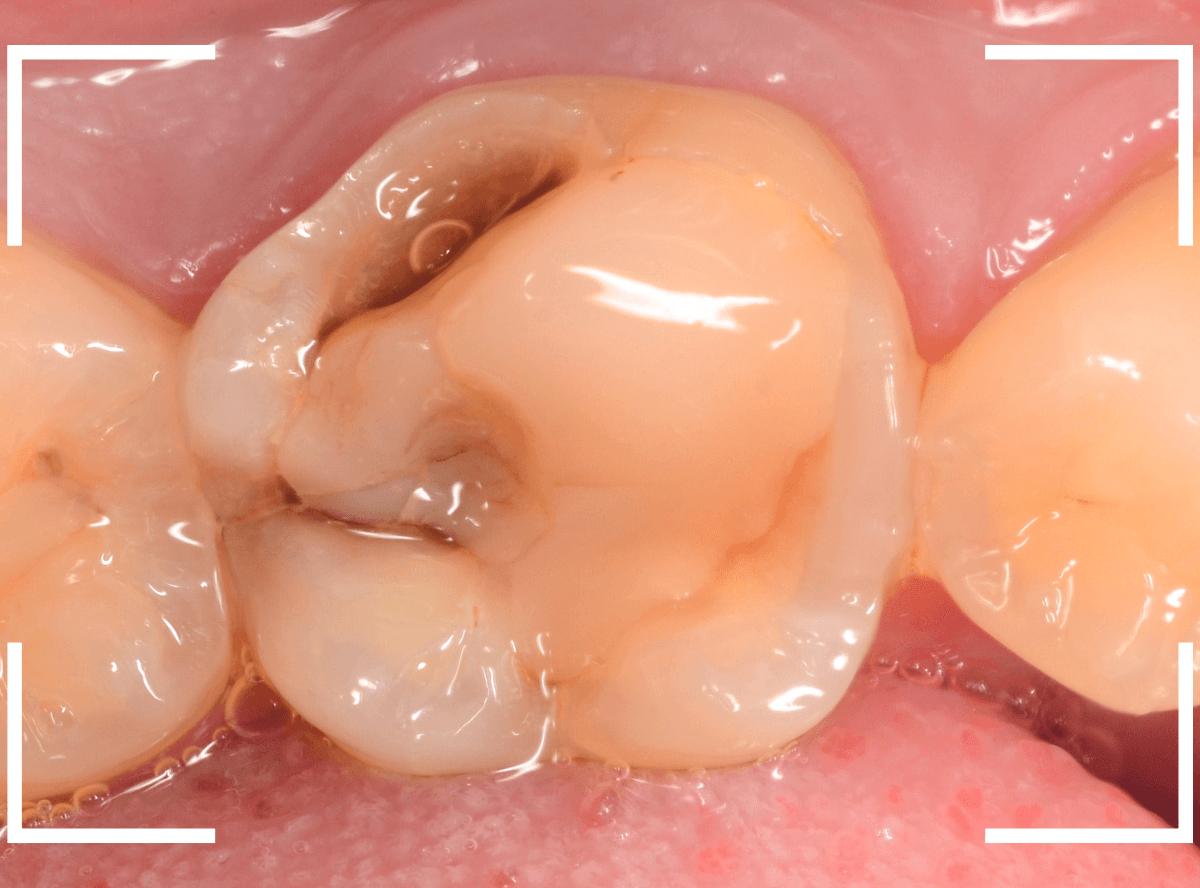

Case.20 劣化したレジン側面から進行した虫歯

「つめものが欠けたまま長期間放置して、歯がしみる」という訴えで来院された患者さんさんです。

拝見すると、劣化したレジンが欠けて、中で虫歯になっているのがわかります。

・欠けたまま長期間放置した

・しみるという自覚症状がある

事から、中で深い虫歯になっている事が想像されます。

レントゲン写真で確認します。